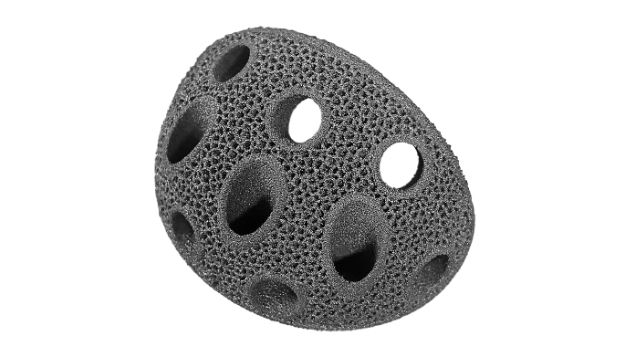

–Ъ–Њ–Љ–њ–Њ–љ–µ–љ—В—Л –≤–µ—А—В–ї—Г–ґ–љ–Њ–є –≤–њ–∞–і–Є–љ—Л MH